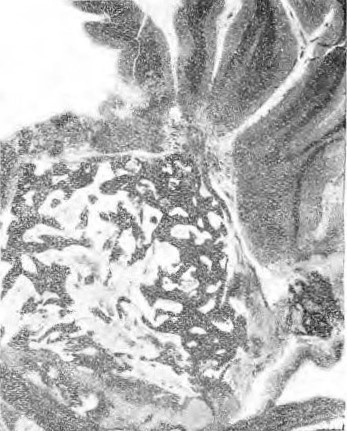

Мозговыя оболочки не представляютъ ничего особеннаго. Вены мягкой мозговой оболочки слегка расширены. Извилины мозга нормальной конфигураціи. При проведеніи фронтальнаго разрѣза въ области центральной доли ножъ въ области полосатаго тѣла наткнулся на твердое тѣло, занимавшее большую часть nuclei lentiformis et caps. int d. и простирающееся кнаружи въ бѣлое вещество до коры insulae Reilii и книзу почти до согни inf. ventriculi lateralis. Описанное твердое тѣло повсюду внѣдрено въ мозговое вещество, изъ котораго оно не выдѣляется. Его поверхность покрыта выступами и зазубринами. Продольный размѣръ его 2,3 сант.; поперечный почти 2 сант. См. рис. 1.

Рис.1

Эта жировая ткань есть костный мозгъ, заполняющій просвѣты губчатаго вещества. Ср. рис. 2. Въ костномъ мозгу виднѣются одиночныя, красныя, содержащія ядра кровяныя тѣльца (нормобласты). У полюса этого образованія, наиболѣе глубоко внѣдреннаго въ мозжечекъ, образованіе кости менѣе замѣтно; здѣсь основа ткани состоитъ изъ плотныхъ, тѣсно сплетенныхъ волоконъ соединительной ткани, въ которой виднѣются одиночные известковые островки; здѣсь дѣло идетъ, стало быть, не о костномъ веществѣ, но объ инкрустаціи соединительной ткани въ видѣ отдѣльныхъ пятенъ. Кромѣ значительныхъ известковыхъ островковъ въ соединительнотканномъ веществѣ находятся еще участки, гдѣ известь расположена въ видѣ зернышекъ и конгломератовъ, диффузно окрашивающихся гематоксилиномъ.

Рис. 2

Исходная точка костныхъ образованій по всей вѣроятности лежала въ мягкой оболочкѣ мозга; тканъ послѣдней столь нѣжна, основа, къ которой прилегаетъ остеома, столь малой прочности, что, какъ указываетъ Пожарійскій, невозможно прослѣдитъ ея анатомическія отношенія. На препаратахъ изъ corpus striatum опухоль имѣетъ приблизительно величину вишневой косточки и лежитъ, какъ инородное тѣло, рѣзко ограниченное въ окружающемъ мозговомъ веществѣ, отъ котораго она все же отдѣлена какъ бы щелью. Строеніе опухоли и здѣсь даетъ картину губчатаго костнаго вещества съ толстыми перекладинами. Большіе участки поперечнаго разрѣза образованы соединительной тканью, подвергшейся разлитому объизвестленію, не обнаруживающей костнаго характера. Вся краевая зона опухоли состоитъ изъ подобной широкой соединительно тканной массы, въ которой произошелъ процессъ диффузнаго объизвсствленія.

Капсула, окружающая кость, состоитъ изъ фиброзноволокнистой, интенсивно окрашенной эозиномъ ткани; волокна ея толсты, гіалиново перерождены, ядра почти отсутствуютъ. Въ отдѣльныхъ мѣстахъ видно, что щель образована искусственно, а что широкіе соединительно тканные тяжи съ расширенными сосудами проникаютъ въ окружающее вещество мозга со стороны капсулы. Между веществомъ мозга и опухолью протянуты мостики рыхлой соединительной ткани. Кромѣ крупныхъ неправильной формы костныхъ перекладинъ находятъ также узкіе костные тяжи. Костный слой выдѣляется своимъ гомогеннымъ основнымъ веществомъ и внѣдренными ядрышками съ типичными отростками; въ костныхъ тѣльцахъ клѣтки большей частью сохранены.

Костныя полости и тѣльца обнаруживаютъ большей частью нормальное строеніе. Клѣтки большей частью ясно зазубрены. Ядра костныхъ тѣлецъ въ отдѣльныхъ мѣстахъ не окрашиваются. Кость какъ видно можетъ также погибнуть, некротизироваться и въ живомъ организмѣ. Говерсовы каналы и пластинки находятся почти вездѣ. Пластинки расположены или параллельно поверхности кости или концентрически. По краю кости только изрѣдка виднѣются единичные остеобласты. Во многихъ мѣстахъ видно, какъ кость безъ рѣзкихъ границъ переходитъ въ окружающую соединительную ткань, и какъ она возникаетъ въ новообразованной соединительной ткани. Очень рѣдко въ единичныхъ мѣстахъ можно констатировать переходъ фибробластовъ въ остеобласты. Развившаяся костная ткань является такимъ образомъ, какъ и нормальная, высокодифференцированнымъ органоиднымъ образованіемъ. Она имѣетъ пластинчатое межклѣточное вещество, костныя тѣльца, лакуны, костно-мозговыя полости и пронизана Говерсовыми каналами. Ни періоста, ни хряща нигдѣ не видно. Нигдѣ нѣтъ слѣдовъ прогрессивнаго процесса. Нигдѣ не видно ни слѣдовъ дальнѣшаго роста кости, ни отпрысковъ описаннаго образованія ни роста опухоли но краямъ. Образованіе производитъ впечатлѣніе, что первичный очагъ подвергся окостенѣнію безъ увеличенія въ объемѣ, окружающее мозговое вещество находится въ состояніи размягченія.